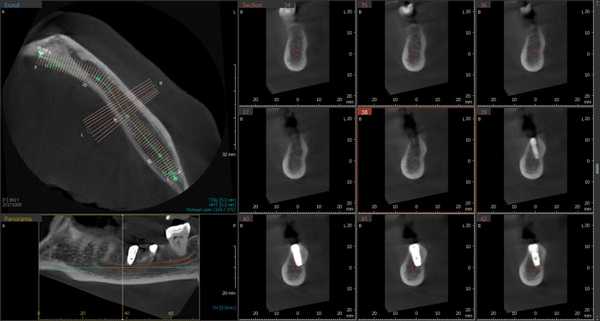

Первая - легкая степень обусловливалась сдавлением ствола за счет отека, гематомы или прямой, непосредственной, но незначительной компрессией имплантатом. Рентгенологическое исследование посредством конусно-лучевой компьютерной томографии и программного обеспечения Ez3D-iV4.3.0 от Vatech, при маркировке нижнечелюстного канала, установило расположение дентальных имплантатов непосредственно у нижнечелюстного канала или эндопротезы перфорировали верхнюю стенку канала (Рис.2). Тактика лечения такого вида патологии основывается на сохранении имплантатов, назначении витаминов группы В, средств, оказывающих непосредственное стимулирующее влияние на проведение импульса по нервным волокнам, усиливающих сократимость гладкомышечной мускулатуры под влиянием агонистов ацетилхолиновых, адреналиновых, серотониновых, гистаминовых и окситоциновых рецепторов. Нарушение чувствительности во всех наблюдениях этой группы носило временный характер и восстановилось через 4–6 недель.

Рис.2 Конусно-лучевая компьютерная томография от Vatech. Нижнечелюстной канал маркирован с помощью программного обеспечения Ez3D-iV4.3.0.